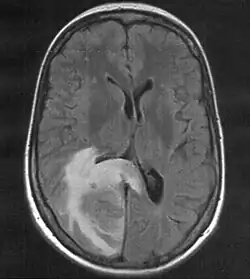

Hirnmetastase

MRT mit T2-Flair-Wichtung, die zugehörige PET-Untersuchung ist weiter unten abgebildet.